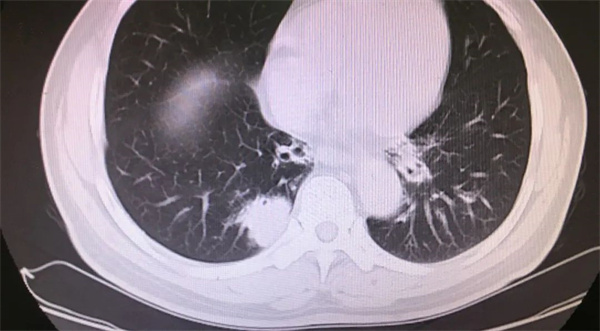

患者吴先生,在我院消化内科住院期间,胸部CT检查发现右下肺结节(直径约2.6cm)。经呼吸与危重症医学科会诊后,于内镜中心及疼痛科大力协助,呼吸内镜团队成功进行无痛超声支气管镜检查并明确病变性质。患者的病灶位于肺外周、靠近脊柱,通过CT发现电子支气管镜无法到达病灶,肺穿刺有肋骨遮挡,为明确诊断,呼吸内镜团队分析讨论后,决定采取内镜超声技术-“R-EBUS-TBLB”(简称“小超”)。术中,经常规支气管镜检查未发现右下肺后基底段管腔内病变,经R-EBUS成功探查到肺外周病灶,撤出超声探头,将活检钳顺利取出4块组织送检,病理提示“低分化腺癌”,为患者下一步治疗提供依据。